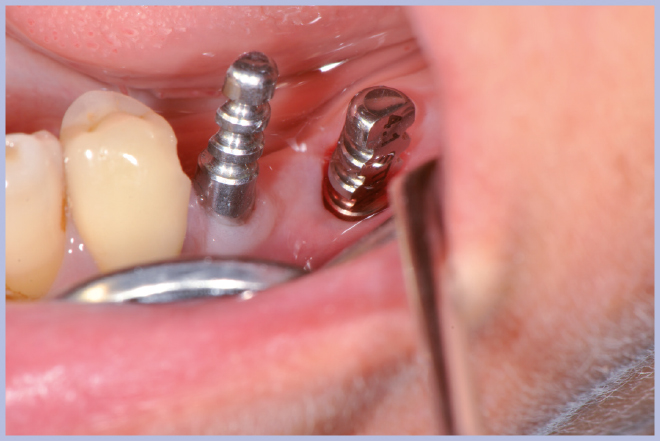

Viene quindi richiesto al tecnico di modificare in laboratorio la mascherina radiologica mediante il posizionamento delle boccole di guida adatte agli impianti da posizionare (Exacone® 6.5 e Exacone® 3,3×8) in asse con gli analoghi del modello Master 3D ed eliminando il repere radiologico standardizzato, trasformandola così nella dima chirurgica (Figg. 14, 15). Si procede quindi alla prova della mascherina sulla paziente per verificarne la stabilità e la corrispondenza esatta con il modello Master 3D (Fig. 16). La seduta chirurgica con tecnica flapless, guida chirurgica e Frese Zero1 dedicate non presenta alcuna difficoltà ; al termine dell’inserimento si posizionano sugli impianti tappi di guarigione bassi per permettere loro di guarire con tecnica sommersa (Figg. 17-27). Si effettua nella stessa seduta una CBCT che dimostra che la posizione clinica degli impianti risulta sovrapponibile a quella progettata dagli Autori (Figg. 28-30).

- Figg. 23-27 – Procedura guidata per inserimento impianto corto Exacone® 6.5

- Fig. 24

- Fig. 25

- Fig. 26

- Fig. 27